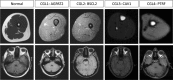

Marrow adipose tissue (MAT) is functionally distinct from both white and brown adipose tissue and can contribute to systemic and skeletal metabolism. MAT formation is a spatially and temporally defined developmental event, suggesting that MAT is an organ that serves important functions and, like other organs, can undergo pathologic change. The well-documented inverse relationship between MAT and bone mineral density has been interpreted to mean that MAT removal is a possible therapeutic target for osteoporosis. However, the bone and metabolic phenotypes of patients with lipodystrophy argues that retention of MAT may actually be beneficial in some circumstances. Furthermore, MAT may exist in two forms, regulated and constitutive, with divergent responses to hematopoietic and nutritional demands. In this review, we discuss the role of MAT in lipodystrophy, bone loss, and metabolism, and highlight our current understanding of this unique adipose tissue depot.